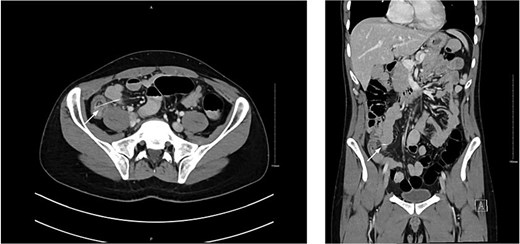

A computed tomography (CT) scan of the abdomen and pelvis revealed a linear hyperdense structure measuring 3.7 cm in length appearing inside the terminal ileum exiting the lumen medially towards the small bowel loops with no signs of free air, likely representing an ingested bone. There was an edematous wall thickening of the cecum and mucosal hyperenhancement of the appendix, which was likely reactive (Fig. 2).

CT scan showing linear hyperdense structure (arrow) within the terminal ileum perforating medially.